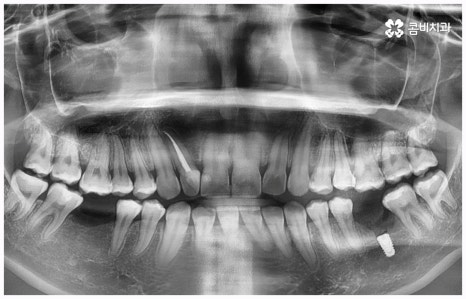

임플란트 종류 는 환자분들의 상황에 따라 달라지기 때문에 먼저 꼼꼼하게 정밀 검진을 받아보고 숙련된 의료진과 충분히 상담을 해 볼 필요가 있습니다. 환자분들의 치아 및 잇몸과 뼈의 상태, 전신 건강 등을 종합적으로 살펴보고 만약 필요하다면 선행 치료부터 받게 될 거예요. 선행 치료는 보통 임플란트 식립을 하게 된 치아 상실의 원인, 그리고 치아가 상실된지 얼마나 오랜 시간이 흘렀는지 여부에 따라 달라지는데 예를 들어 비교적 어린 나이에 큰 사고를 당해서 치아를 잃게 되었을 때 지체없이 바로 치과로 내원한 경우, 잇몸뼈가 건강하고 나이 등 회복력에 대한 기대치도 높은 편이며 다른 전신 질환, 상용약 등 잇몸에 지속적인 영향을 줄 만한 요소가 없다고 한다면 별다른 선행치료 없이 임플란트 종류 중 당일 심고 바로 임시 치아로 식사를 할 수 있는 원데이 임플란트를 통해 보다 빠르고 간편한 수복을 할 수 있어요.

보통은 인공 치근을 식립한 후에 얼마 동안 시간을 두어 골유착이 잘 일어나게 한 후에 지대주(연결 부위)를 연결하고 크라운 보철물을 제작, 장착해 주는데 여기서 개개인의 상황이 모두 다르기 때문에 회복 기간이 얼마나 걸릴지 정확하게 알 수는 없지만 대부분 3~6개월 정도라고 보면 될 거예요. 그동안은 불편한 상태로 사용을 할 수 밖에 없는데 만약 검진 및 발치, 식립, 임시 치아 제작 및 장착까지 모두 하루 만에 이루어진다면 임플란트 치료 기간을 줄일 수 있을 뿐 아니라 내원 횟수 및 통증과 불편감 또한 감소시킬 수 있을 것이기 때문에 시간적인 여유가 많지 않은 직장인분들, 학생들, 유학생분들이나 지방에 거주하시는 분들과 같은 경우에 임플란트 종류 중 원데이 임플란트 식립에 대해서 관심을 많이 보이고 있습니다. 그러나 말씀드린 것처럼 누구나 받을 수 있는 것은 아니기 때문에 먼저 잇몸뼈의 상태를 꼼꼼하게 체크하여 가능성 여부를 알아볼 필요가 있으니 검진 및 상담부터 진행해 보시길 권유드리고 있어요.

비용이나 시간적인 부담이 만만치 않기 때문에 임플란트를 보다 오랜 기간 동안 건강하게 사용하려면 어떻게 해야 하는지 궁금해 하시는 분들이 많이 있으실 거예요. 임플란트 식립 성공률 및 지속률에 가장 크게 영향을 주는 것은 환자분들의 잇몸뼈 건강 상태 및 술자의 숙련도라고 할 수 있는데요. 예를 들어 구강 질환을 원인으로 한 병증이 심각하거나 치아를 상실한지 오랜 시간이 지나 잇몸뼈의 흡수가 많이 일어났기 때문에 높이와 밀도 등이 식립을 진행하기에 충분하지 않다면 뼈이식을 선행하여 기반부터 튼튼하게 보충해 줄 필요가 있어요. 또한 노화로 인해 상악동이 내려왔다면 상악동 거상술을 통해 공간을 확보해 주어야 하는데 이렇게 고난도 수술의 경우 다양한 임상 경험을 통해 풍부한 노하우와 뛰어난 기술력을 가지고 있는 의료진과 함께 하는 것이 무엇보다 중요하다고 할 수 있습니다.